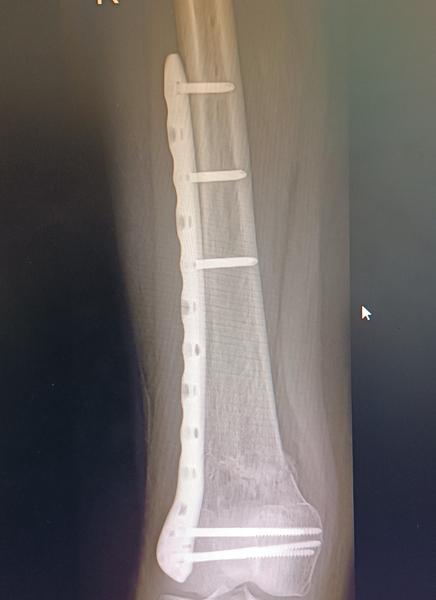

@minenkaa aj mne dávajú na výber jeden doktor bol zato vybrať kvôli veku a tomu že pri dlhšej chodzi mi začne platnička tlačiť na koleno a boli ma skôr sa mi zdalo že v zime to bolo viac ..dnes som bola už teda dohodnúť operaciu a tam iny doktor že by to tam možno aj nechal že na mojom mieste že zas mi to narežu v mieste jazvy a narušia tkaniva a niekedy sa to ani nejak nezlepší že keď tam už bolo zranenie neviem sama čo robiť som s toho na nervy 🙁bojim sa operácie hrozne ale aj toho že mi tam ta platnička bude vadiť keď nastupim do prace ešte som na materskej

@anonym_a80ec7 ano po prvej operácii som si vravela že nikdy viacej že to tam necham navždy ale teraz ..vaham lebo ma boli koleno z toho keď dlho chodim ta platnička tlačí naň preto zvažujem vybratie viem že to tam môže byť navždy len sa bojim aby mi to neskôr nerobilo vetšie problemy .